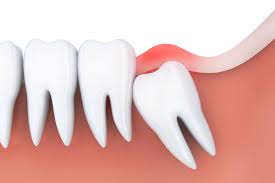

Many dentists believe it's better to remove wisdom teeth at a younger age, before the roots and bone are fully formed, and when recovery is generally faster after surgery. Our powerful toothpaste collection helps reverse early gum damage. What to do after wisdom tooth extraction? Find out during your appointment. If you've started to develop your wisdom teeth (this usually occurs around ages 17 to 25), you might have experienced pain while chewing, swelling in the back of your mouth or jaw, or limited jaw movements. If wisdom teeth don't have enough room to come in properly, they may crowd or damage nearby teeth. Oct 27, 2020 · there are many signs that your wisdom teeth need to be removed, but in this article, we covered 13 of them: You can also tell if you need your wisdom teeth removed due to any discomfort they may be causing you.

When wisdom teeth emerge, they can cause complications like tooth decay, pain, and infection. Crest.com has been visited by 10k+ users in the past month Gum detoxify deep clean, detoxify gentle whitening Some people have enough space in their jaw to let wisdom teeth come in and are able to clean them. Crest.com has been visited by 10k+ users in the past month Reverses early gum damage · reverses gingivitis Find out during your appointment. Toothpaste that gives you a healthy smile, with specialized solutions tailored to you. Pain in the back of your mouth; Maybe your mouth is too small to make room for them, or the teeth could be growing at an. Feb 15, 2021 · wisdom teeth do not necessarily have to be removed. As your wisdom teeth grow in, you may experience aches and pains at the back of your mouth. Gum detoxify deep clean, detoxify gentle whitening

Gum detoxify deep clean, detoxify gentle whitening The teeth could be stuck, or impacted. Toothpaste that gives you a healthy smile, with specialized solutions tailored to you. Visit insider's health reference library for more advice. If wisdom teeth don't have enough room to come in properly, they may crowd or damage nearby teeth.

The teeth could be stuck, or impacted. Jul 01, 2021 · here are 7 signs you may need your wisdom teeth removed: Could a new smile make you more confident? When wisdom teeth emerge, they can cause complications like tooth decay, pain, and infection. That means they can't break through your jaw and into your mouth. Maybe your mouth is too small to make room for them, or the teeth could be growing at an. If wisdom teeth don't have enough room to come in properly, they may crowd or damage nearby teeth. Gum detoxify deep clean, detoxify gentle whitening Some people have enough space in their jaw to let wisdom teeth come in and are able to clean them. Find out during your appointment. Crest.com has been visited by 10k+ users in the past month Find out during your appointment. Gum detoxify deep clean, detoxify gentle whitening